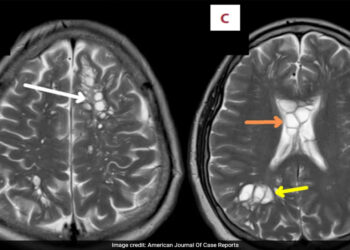

ആശുപത്രിയിൽ എത്തിയത് കടുത്ത തലവേദനയെ തുടർന്ന്: തലച്ചോറിൽ കണ്ടെത്തിയത് പന്നിയിറച്ചിയിൽ കാണുന്ന നാടവിരകൾ

കഠിനമായ മൈഗ്രൻ ബാധിച്ച് ആശുപത്രിയിൽ എത്തിയ 52 കാരൻ്റെ തലച്ചോറിൽ നാടവീരകൾ കണ്ടെത്തി. ന്യൂയോർക്ക് പോസ്റ്റിന്റെ റിപ്പോർട്ട് അനുസരിച്ച് യുഎസ് പൗരനായ വ്യക്തിക്ക് കഴിഞ്ഞ നാല് മാസമായി ...